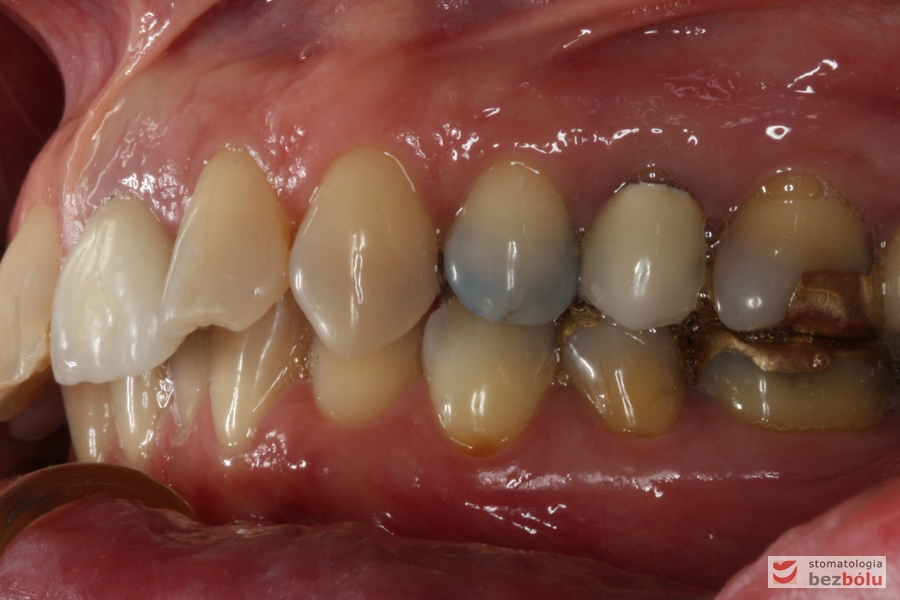

Do naszej placówki zgłosiła się starannie planująca swoje działania Europejka, mieszkająca na stałe w Kotlinie Jeleniogórskiej. Jej oczekiwania dotyczyły bardzo metodycznie zaplanowanego planu leczenia. Celem jaki postawiła przed naszym zespołem lekarzy było wyeliminowanie wszystkich wątpliwych i nierokujących wypełnień, a także poprawa estetyki w zakresie lewego siekacza centralnego w szczęce. Został rozpisany blisko dwuletni plan wymiany zużytych i nieszczelnych wypełnień amalgamatowych i kompozytowych. Zaplanowano również przygotowanie endodontyczne wybranych zębów w szczęce i żuchwie, a także zaopatrzenie w inlay’e porcelanowe i korony ceramiczne wykonane w systemie e-max.